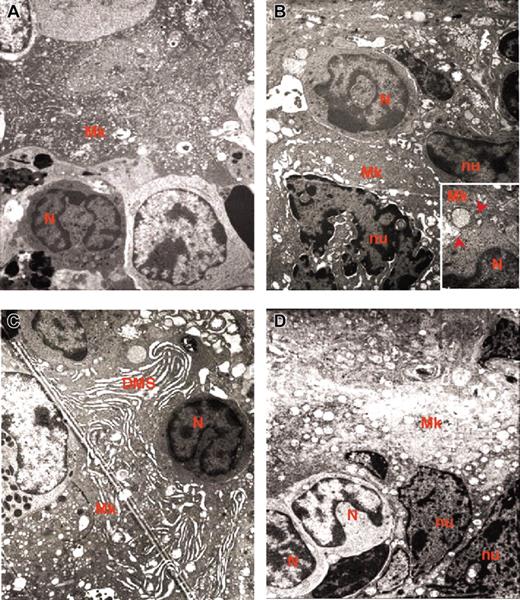

The abnormal P-selectin localization on the DMS of the heavy electron-dense mutant MKs prompted us to analyze the reciprocal distribution of MKs and neutrophils in the spleen from normal and GATA-1low littermates. As expected, very few (0.07 × 103/cm2) neutrophils are recognized on spleen sections from normal animals.18,19 In contrast, as many as 103/cm2 neutrophils are identified on sections from the same region within the white and red pulp of the GATA-1low spleen where are also found high numbers of MKs. Furthermore, as many as 40% of the heavy electron-dense GATA-1low MKs are engulfed with other cell types. More precisely, 16% to 19% (in the spleen) and 32% to 34% (in the marrow) of heavy electron-dense MKs contain neutrophils (Table 1). All the steps of neutrophils establishing contacts with MKs can be identified in sections from the spleen of the mutant mice. Examples of a neutrophil approaching an MK, touching the MK plasma membrane, and fusing its membrane with that of the MK, starting to enter the MK via the dysmorphic DMS and completely enclosed in the MK cytoplasm are shown in Figure 6. Up to 3 neutrophils are found embedded into heavy electron-dense MKs.

Sequential phases of neutrophil emperipolesis in MKs from the spleen of GATA-1low mouse. The different panels present a neutrophil (N) approaching the MK (A); establishing contacts with the MK (B) and fusing its own membrane with that of the MK (arrowheads in the insert in panel B); penetrating the MK through the DMS (C). Finally, panel D shows 2 neutrophils enclosed inside the MK cytoplasm. Note that in this last case, the MK cytoplasm appears highly vacuolated, a sign of cell damage, whereas the cytoplasm of the neutrophil appears degranulated. Nu indicates nuclear area of the MK. Original magnification × 3000 for all panels and × 30 000 for the insert.